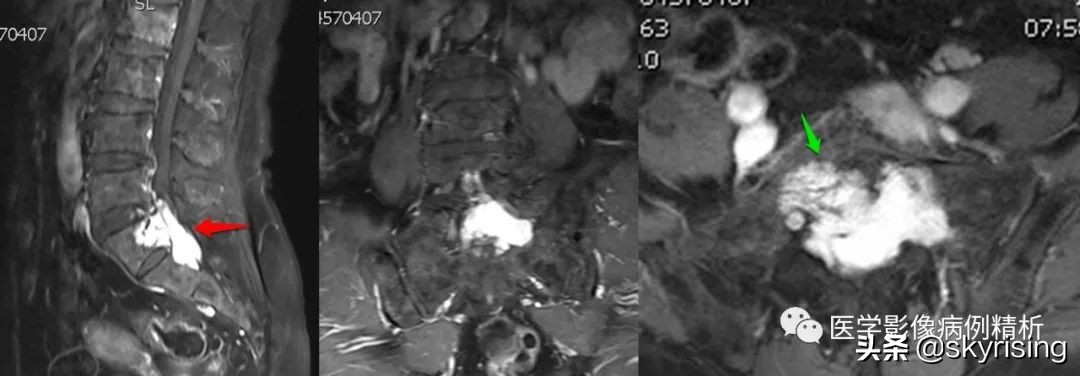

如图所示,红色箭头可见不规则形异常信号,轴位呈哑铃型,病灶前缘侵及骶1、2椎体后缘,绿色箭头见骨质局部破坏,病灶T1低信号,T2稍高信号,压脂像明显高信号,信号尚均匀,腰4-5、腰5骶1椎间盘向后方突出,硬膜囊受压,蓝色箭头可见腰4-5椎间盘后缘纤维化小点状T2高信号,提示纤维环后缘撕裂。本例骶1-2椎间盘形成,骶1椎体腰化不完全。

如图所示,分别为T1WI增强矢状位、冠状位、轴位,T1WI增强矢状位与T2WI压脂像非常相像,注意椎管内脑脊液信号,T1WI增强为低信号与T2WI压脂像高信号正好相反。红色箭头所示病灶明显强化,呈亮灯征感觉,清晰显示病灶范围,绿色箭头所示为病灶侵及骶1椎体后缘形成不规则形骨质破坏区。

红色箭头:病灶位于骶1-2椎体水平,轴位呈哑铃型,CT见骶1-2椎体后缘受侵、骨质破坏;MRI见病灶主体沿骶管及双侧骶孔生长,以左侧骶孔为著,T1低信号,T2稍高信号,压脂像高信号,接近脑脊液信号。

绿色箭头:骶1-2椎体后缘见信号向内部侵犯,边缘毛糙。